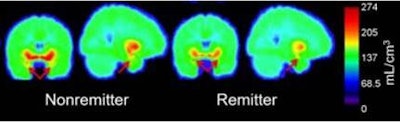

Ananth and colleagues found a significant difference in amygdala binding, with medication-free patients showing 11% less amygdala binding than the controls. They suggested that 5-HTT amygdala binding should be studied further as a possible biomarker for remission after treatment with escitalopram.

"Our results indicate that patients who found relief following escitalopram treatment had less 5-HTT protein before treatment began," Ananth said. "This is exciting because it suggests that pretreatment neurobiology can be used to predict response to treatment, potentially preventing ineffective treatment trials."